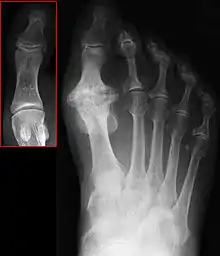

Hallux not labeled but visible at upper left. | |

Hallux rigidus or stiff big toe is degenerative arthritis and stiffness due to bone spurs that affects the metatarsophalangeal joints (MTP) at the base of the hallux (big toe).